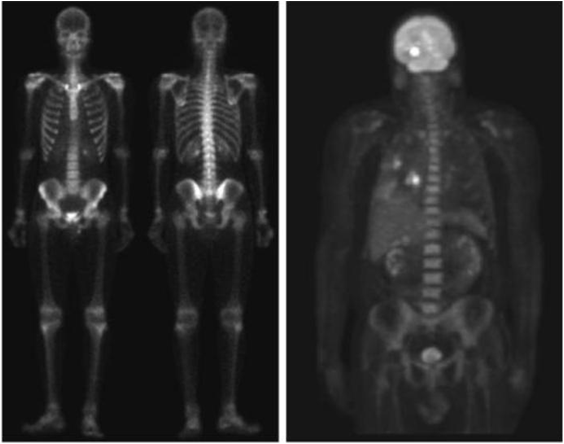

Gamma ray image

• 감마선의 투과성을 이용

• 주요 응용분야: 핵의학, 천문관측

Image

a) 환자에게 감마선을 방사하는 방사선 동위원소를 주사, 감마 검출기로써 영상을 획득 - 병소의 위치 파악에 유용 b) PET(positron emission tomography) image c) 백조자리 15,000년전의 가스성운의 감마선 영상 d) 핵반응 밸브로부터 나오는 감마선(밝은 부분)